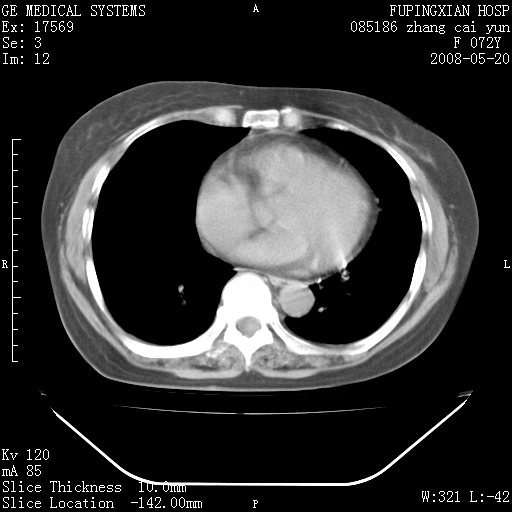

标题: CT13542:发热,咳嗽数日,经抗菌素治疗好转,请大家看排除 [打印本页]

标题: CT13542:发热,咳嗽数日,经抗菌素治疗好转,请大家看排除

右肺上叶实变影,内见支气管充气征,右上叶支气管通畅,肺门区未见软组织密度影,抗炎治疗有效,考虑炎症,建议继续抗炎治疗复查。

右肺阻塞性肺炎  不除外支气管内膜结核

考虑为:右肺上叶感染性病变。建议:1)继续抗炎治疗后复查。2)必要时行纤支镜检查。

右上肺实变,间内有支气管充气征,考虑炎症,建议抗炎后复查